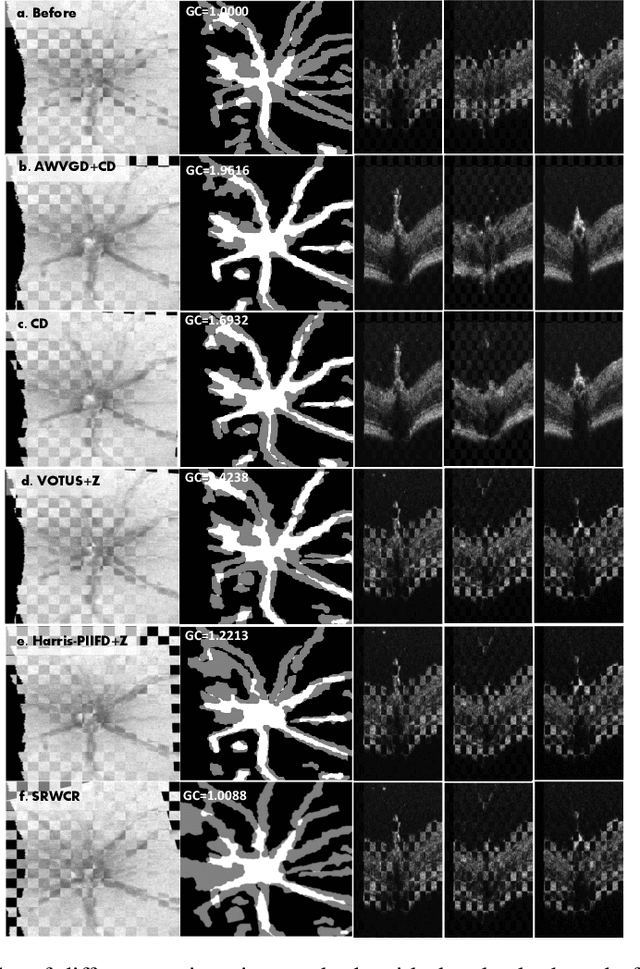

Abstract:Registration of longitudinal optical coherence tomography (OCT) images assists disease monitoring and is essential in image fusion applications. Mouse retinal OCT images are often collected for longitudinal study of eye disease models such as uveitis, but their quality is often poor compared with human imaging. This paper presents a novel but efficient framework involving an optimal transport based graph matching (OT-GM) method for 3D mouse OCT image registration. We first perform registration of fundus-like images obtained by projecting all b-scans of a volume on a plane orthogonal to them, hereafter referred to as the x-y plane. We introduce Adaptive Weighted Vessel Graph Descriptors (AWVGD) and 3D Cube Descriptors (CD) to identify the correspondence between nodes of graphs extracted from segmented vessels within the OCT projection images. The AWVGD comprises scaling, translation and rotation, which are computationally efficient, whereas CD exploits 3D spatial and frequency domain information. The OT-GM method subsequently performs the correct alignment in the x-y plane. Finally, registration along the direction orthogonal to the x-y plane (the z-direction) is guided by the segmentation of two important anatomical features peculiar to mouse b-scans, the Internal Limiting Membrane (ILM) and the hyaloid remnant (HR). Both subjective and objective evaluation results demonstrate that our framework outperforms other well-established methods on mouse OCT images within a reasonable execution time.